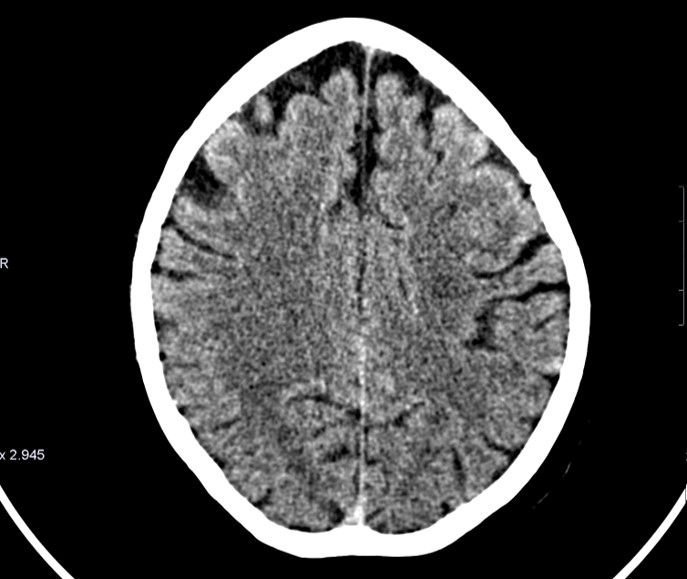

En efecto, el tipo de prueba como método diagnóstico de elección sería la Tomografía Computarizada debido a que es capaz de identificar lesiones que afectan al Sistema Nervioso Central con gran sensibilidad. La segunda opción que puede inducir a duda sería la Resonancia Magnética, sin embargo, se descarta como primera opción debido a que es menos económica que el TC, su realización nos llevaría mayor tiempo, y sobre todo, debido a la escasa disponibilidad de la misma.

Haz click en las imágenes para verlas ampliadas